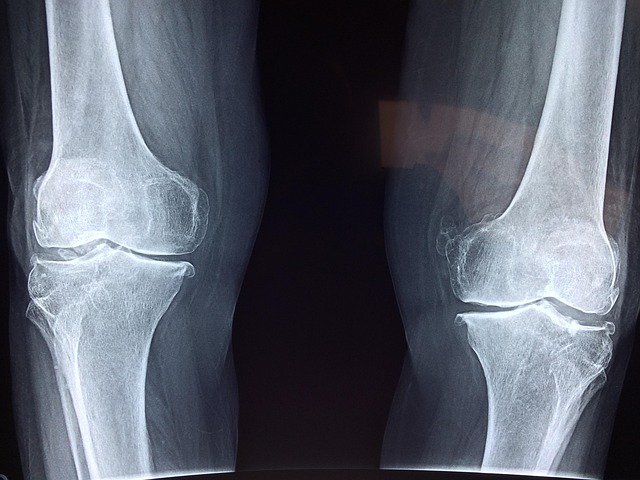

In 2014, a series of strange-looking knee X-rays made their rounds on social media. The x-rays, which revealed hundreds of tiny lines around the knees, have recently reappeared online. The x-rays belonged to a South Korean woman who was 65 years of age at the time. She had previously been diagnosed with osteoarthritis, a condition characterized by the degradation of the bones and cartilage within joints, resulting in stiffness and pain. She had tried many different anti-inflammatories and pain relieving drugs, but none of them worked and only gave a sore stomach. So, left without any other options, she then decided to try acupuncture, which eventually led to the surprising findings on her knee x-rays.

X-Ray Reveals Strange Acupuncture Practice

X-ray of acupuncture needles around knees

Credit: New England Journal of Medicine